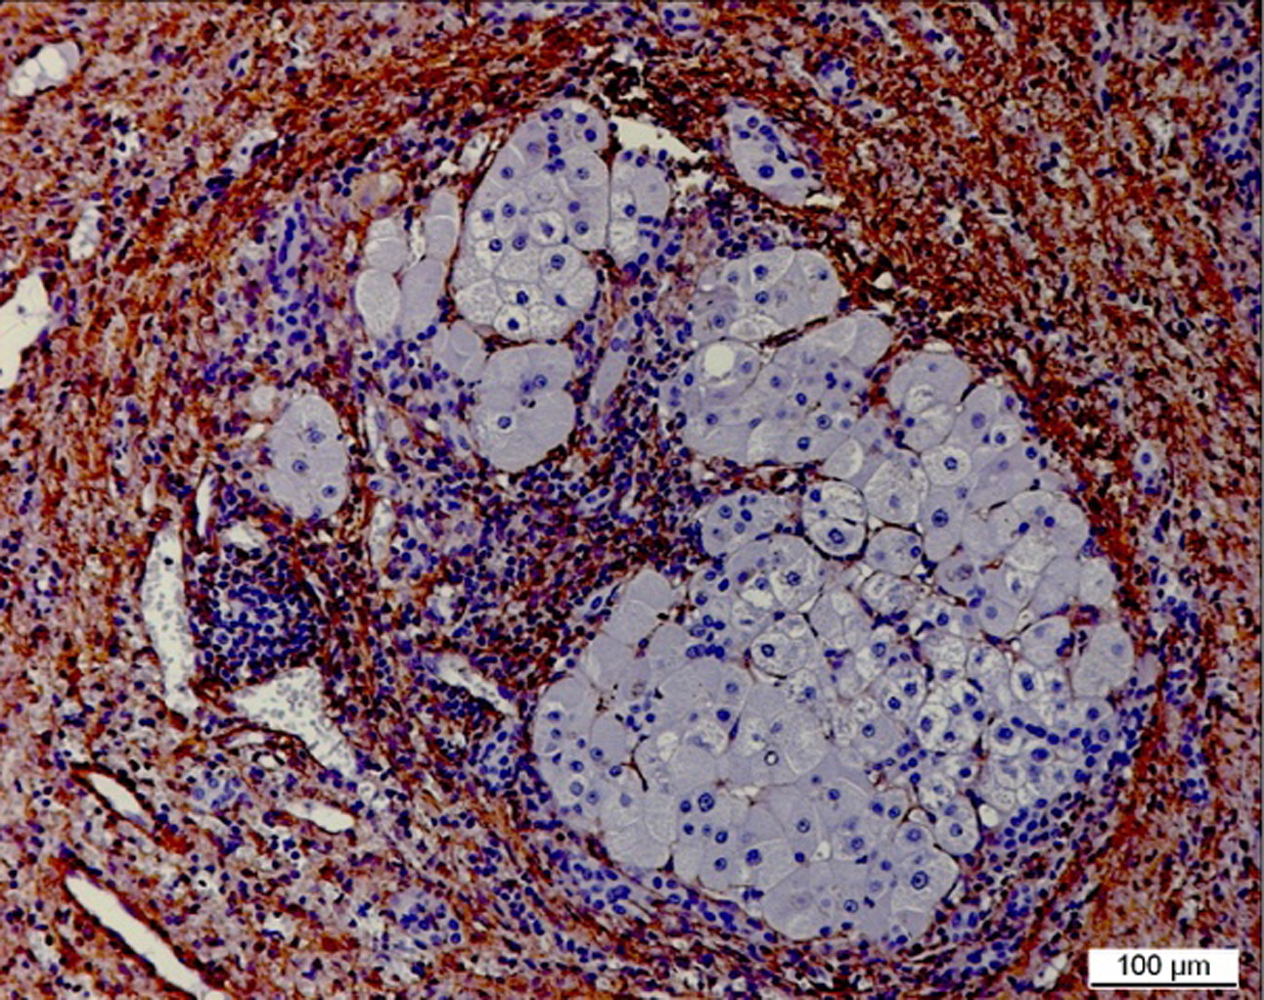

Die Wissenschaftler untersuchen strukturelle Veränderungen der extrazellulären Matrix und der Zellinteraktion in sogenannten zirrhotischen Knoten, die als Kipppunkt (TIP) die Entstehung eines HCC begünstigen. Mittels sogenannter cutting edge Technologien analysieren die experimentellen Arbeitsgruppen die zirrhotischen Knoten in der Umgebung der Hepatozellulären Karzinome und vergleichen sie mit denen in den Lebern tumorfreier Zirrhotiker. Dabei untersuchen sie insbesondere die Matrixzusammensetzung und Veränderungen (fate changes) in den Makrophagen- und Fibroblasten-Zellpopulationen auf Biomarker, die den TIP der Progression zum Krebs charakterisieren.